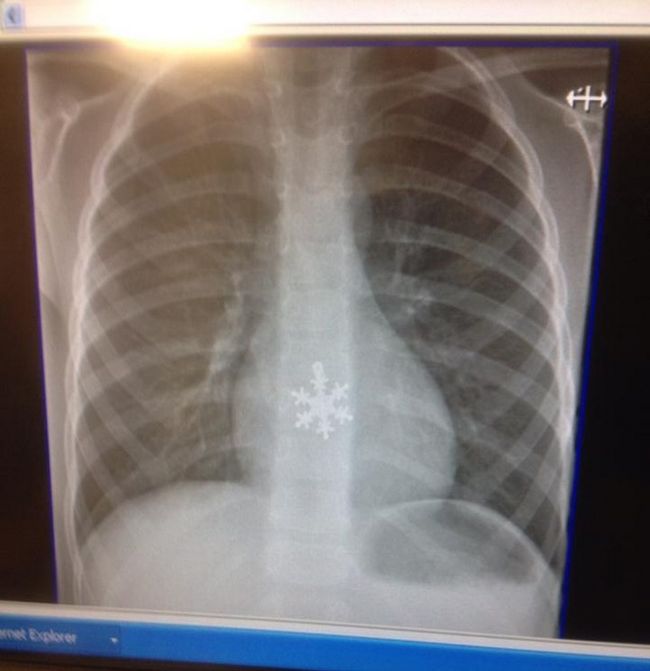

2 – “O filho da minha amiga engoliu um pingente de floco de neve”